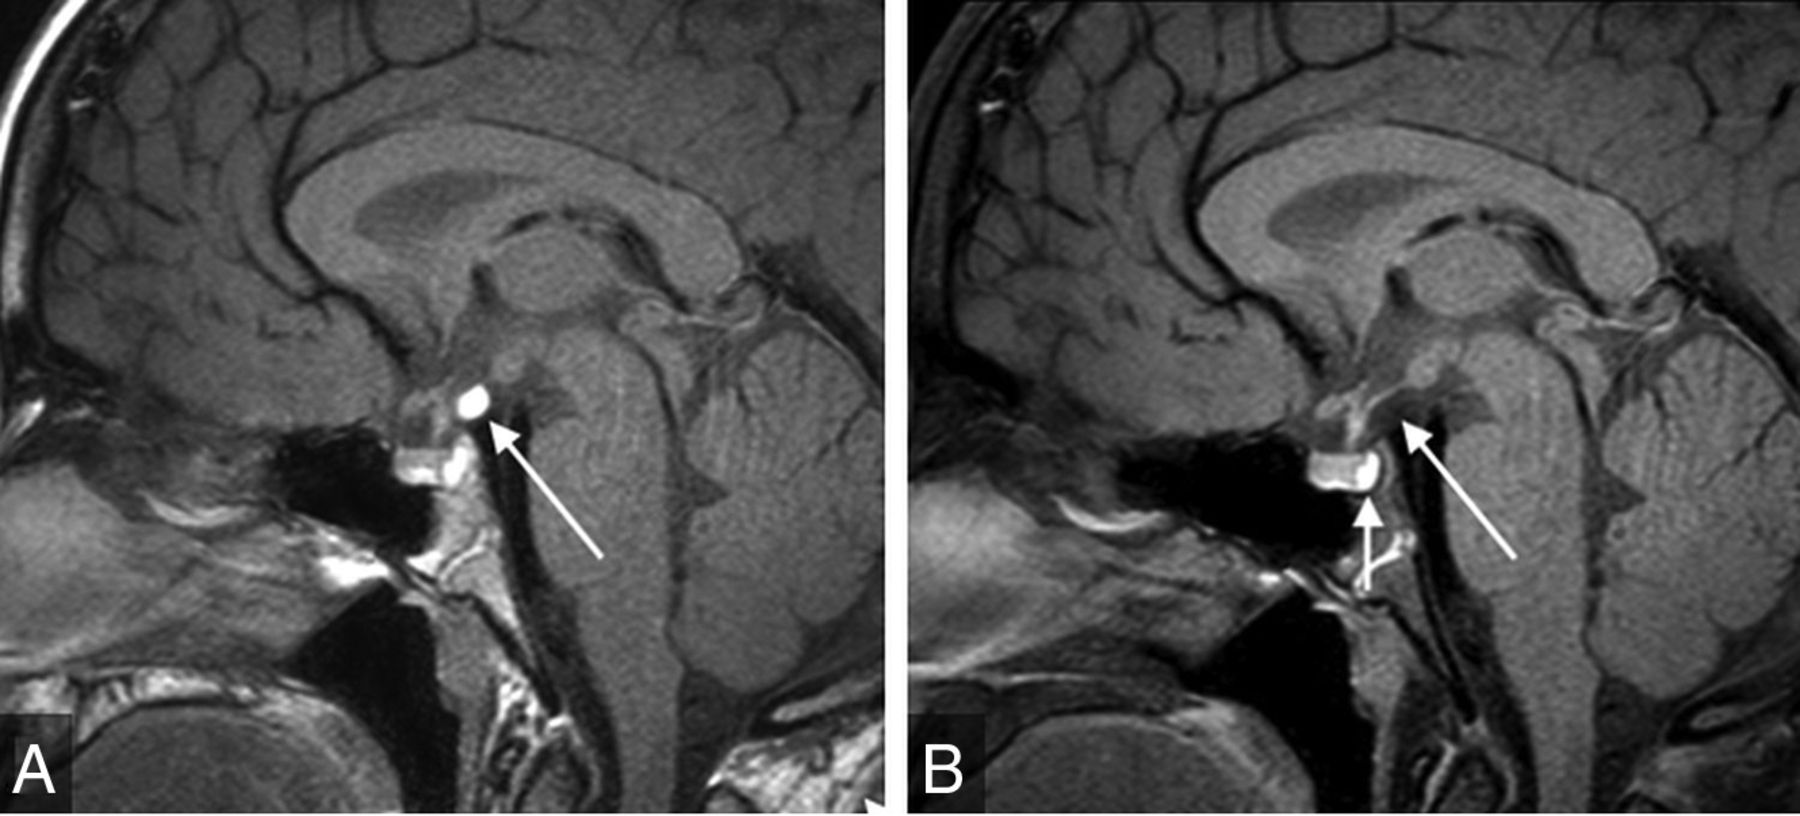

On the basis of the results of our study, we advocate for use of a rapid noncontrast pituitary MR imaging protocol for pediatric patients presenting with GHD, CPP, or SS. This protocol includes coronal and sagittal TSE T1-weighted multipoint Dixon (mDixon) and sagittal T2-weighted thin-section images of the sella, axial T2WI or FLAIR of the brain, and axial DWI (Online Supplemental Data). Depending on institutional preference, thin-section coronal T2WI for evaluation of the optic and olfactory apparatus and hypothalamus may be substituted for or performed in addition to sagittal T2WI, especially in patients with suspected septo-optic dysplasia or Kallman syndrome. The choice of the acquisition technique, such as the section thickness and 2D-versus-3D acquisition, will depend on institutional preference (taking into account the desired length of the rapid examination). When available, scanning should be performed on higher-field-strength magnets (eg, 3T) because increased spatial and image contrast resolution may enhance diagnostic performance. However, it may not be feasible for all scans to be performed on 3T systems due to scheduling and other logistic factors. Coronal and sagittal T1WI of the sella is capable of depicting most relevant anatomic abnormalities, including small anterior pituitary and absent or ectopic posterior pituitary glands. In addition, other midline abnormalities such as callosal malformation are readily detectable. At centers capable of performing mDixon sequences, we propose acquiring mDixon pituitary images because the fat-suppressed images are helpful for differentiating the posterior pituitary gland from clival marrow fat, differentiating ectopic posterior pituitary from lipoma, and evaluating extra-cranial pathology (Fig 5). Thin-section sagittal T2WI is helpful for characterizing sellar cystic lesions, which often have variable signal on T1- and T2WI (Fig 6). Axial T2WI and/or axial FLAIR (depending on institutional preference) and DWI can be helpful in detecting concurrent brain ab-normalities such as signal abnormality concerning for neoplasm, which is a relative contraindication to administration of growth hormone, and cortical malformations that are common in patients with conditions involving the hypothalamic-pituitary axis such as septo-optic dysplasia.10⇓-12

Sagittal mDixon T1WI (A) shows a hyperintense suprasellar mass along the posterior aspect of the infundibulum (long arrow). Sagittal mDixon T1-weighted water-only image (B) shows complete suppression of this mass, which is diagnostic of lipoma. The neurohypophysis is bright on the water-only images and is highlighted against suppressed fat in the dorsum sellae (short arrow, B). mDixon T1WI is helpful for evaluation of fat-containing sellar region lesions and identification of the normal orthotopic neurohypophysis. Furthermore, it can differentiate a fat-containing lesion from ectopic neurohypophysis.

Sagittal T2WI shows a hypointense pars intermedia cyst (arrow) that was not definitely visible on sagittal T1WI (not shown). This case highlights this sequence being complementary to T1WI and helpful for identification and characterization of sellar cystic lesions. It is suggested as part of the rapid noncontrast pituitary protocol because it further decreases the needed for intravenous contrast.